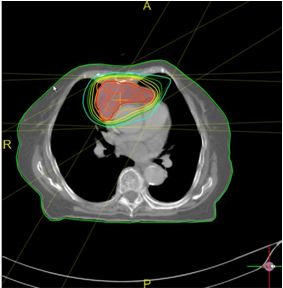

Bệnh nhân được chụp CT mô phỏng để lập kế hoạch xạ trị với kỹ thuật IMRT.

Ngày 20/03/2009: Tiến hành xạ trị với kỹ thuật IMRT

Hình ảnh lập kế xạ trị IMRT

Đồ thị DVH phân bố liều chiếu xạ vào khối và các cơ quan cần bảo vệ

Kết quả cho thấy: Liều xạ trị chiếu vào khối u đạt mức cao nhất, trong khi các cơ quan cần bảo vệ (động mạch chủ, tim, phổi,...) chịu liều không đáng kể. Trong quá trình xạ trị, lâm sàng bệnh nhân không khó thở, huyết động ổn định, không bị gián đoạn xạ trị.